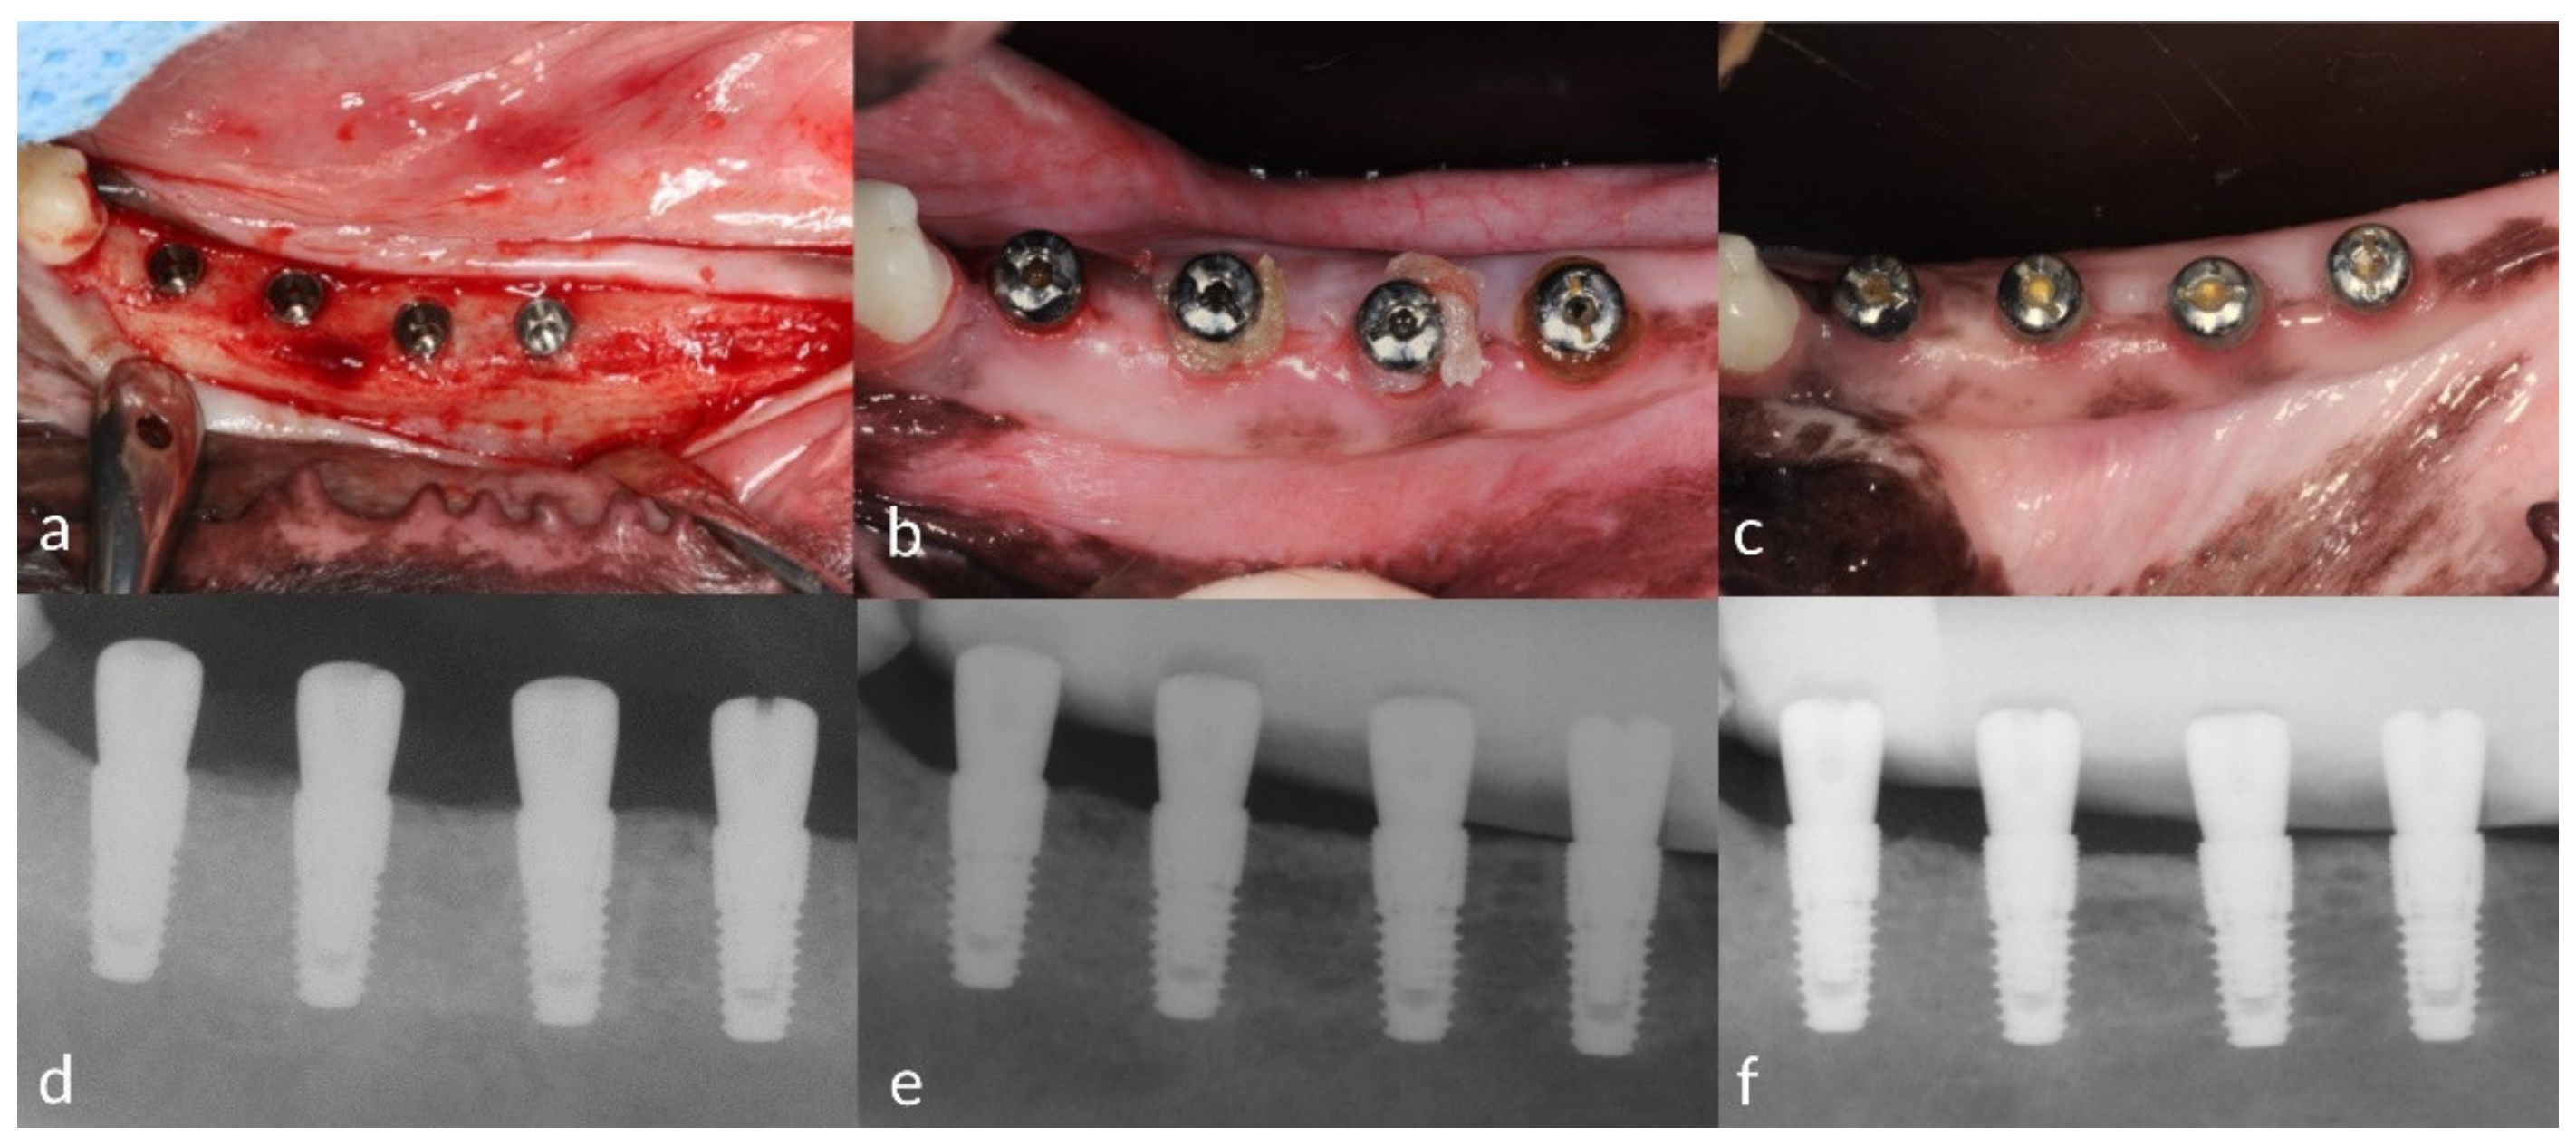

2.3.1. Tooth Extraction and Implant Installation

2.3.2. Experimental Peri-Implant Mucositis

2.3.5. Clinical and Radiographical Outcomes

2.3.6. Histological Preparation and Outcomes

3.3. Radiographical Findings